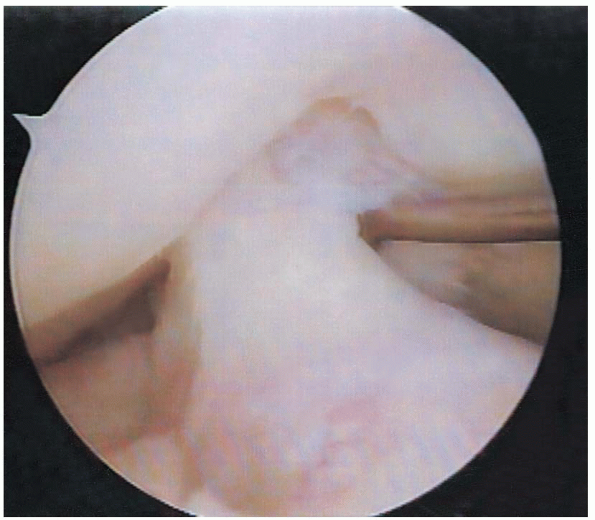

This can prevent inadvertent damage. The lens is then rotated to allow visualization of the anterior horn, body, and posterior horn of the medial meniscus (Figs. 25-14 and 25-15). Under direct visualization, a probe is used to manually palpate the superior and inferior surface of the meniscal tissue.

FIGURE 25-15. Visualization of the body of the medial meniscus, demonstrating a tear.